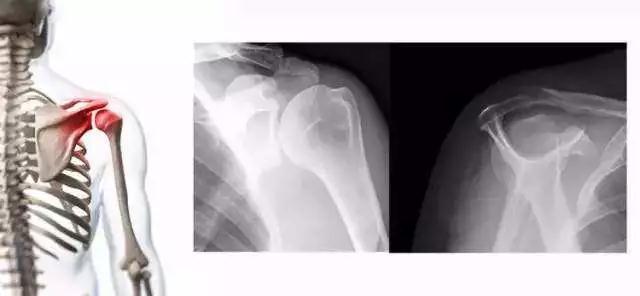

1.X线检查

对判断肩峰的形态及肩关节骨性结构的改变有帮助。部分肩袖损伤患者肩峰前外侧缘及大结节处有明显骨质增生。